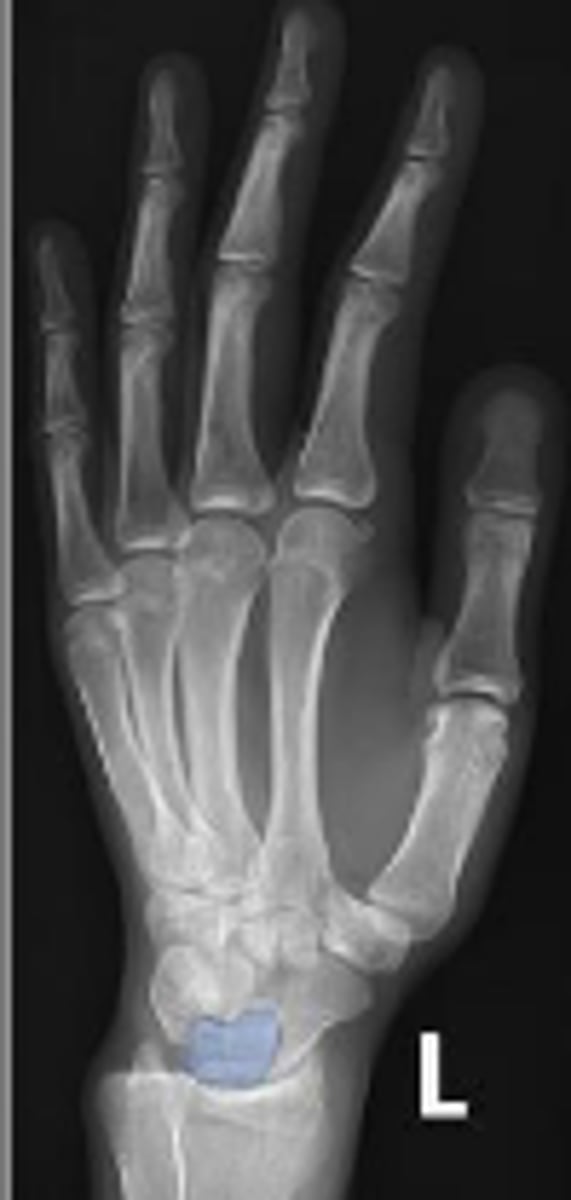

PA of the left wrist

What is the name of the radiographic view?